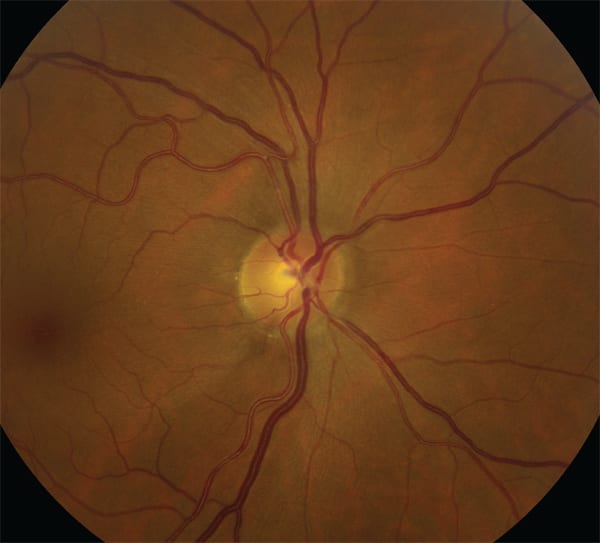

While IOP reduction or increasing ocular perfusion pressure or CSF pressure may protect the optic nerve by altering pressure gradients or optic nerve perfusion, in this discussion we will consider neuroprotection to be agents that directly protect the ganglion cells and their axons. Harry Quigley, MD,7 and others have demonstrated that apoptosis of retinal ganglion cells occurs in experimental glaucoma, and as the Figure demonstrates, the optic nerve head and the RGC axon is the site of glaucomatous optic nerve damage.

Figure: An inferotemporal RNFL defect emanating from the neuroretinal rim illustrates that glaucomatous damage occurs very close to the neuroretinal rim — the only place along the ganglion’s efferent pathway when these fibers are located in close proximity where they might be damaged together.